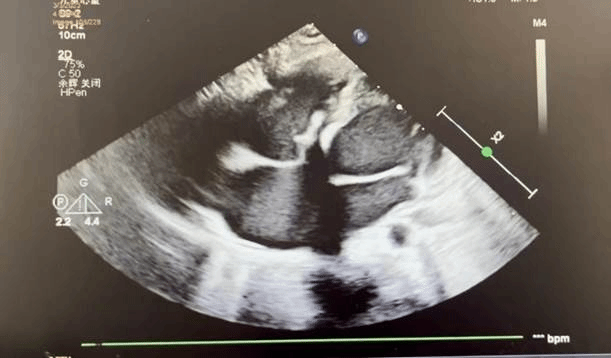

术后超声

术前缜密准备,手术如期举行。麻醉科杨旺主治医师为玲玲进行全麻后,在心内科修丽丽副主任医师的全程超声指导下,张东会副主任医师等人凭借默契的配合、精湛的技术,成功完成手术。术后造影及经胸超声结果显示全降解封堵器形态良好,封堵完全,无残余分流,主动脉无返流,遂完全释放封堵器,回收成型线,封堵效果理想。